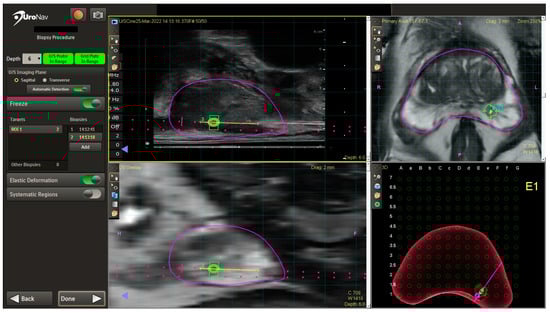

4.2. mpMRI–TRUS Fusion